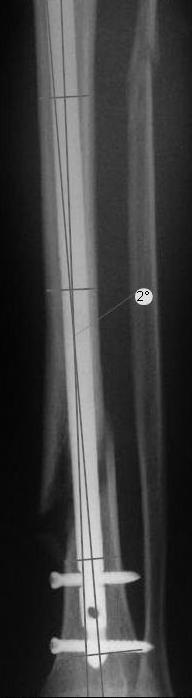

Re: неправильно фиксированный перелом

Вы бы стали оперировать или рекомендовали бы своему родственнику оперироваться из-за 2 градусов?

Динамизировать, выкрутив проксимально все винты, на сроке 8 недель ихмо достаточно.